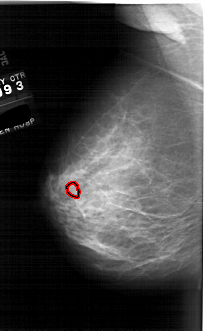

A_1761_1.LEFT_CC

LEFT_CC LINES 6526 PIXELS_PER_LINE 3601 BITS_PER_PIXEL 12 RESOLUTION 43.5 OVERLAY

FILE: A_1761_1.LEFT_CC.OVERLAY

TOTAL_ABNORMALITIES 1

ABNORMALITY 1

LESION_TYPE MASS SHAPE OVAL MARGINS ILL_DEFINED

ASSESSMENT 4

SUBTLETY 3

PATHOLOGY BENIGN

TOTAL_OUTLINES 1

BOUNDARY